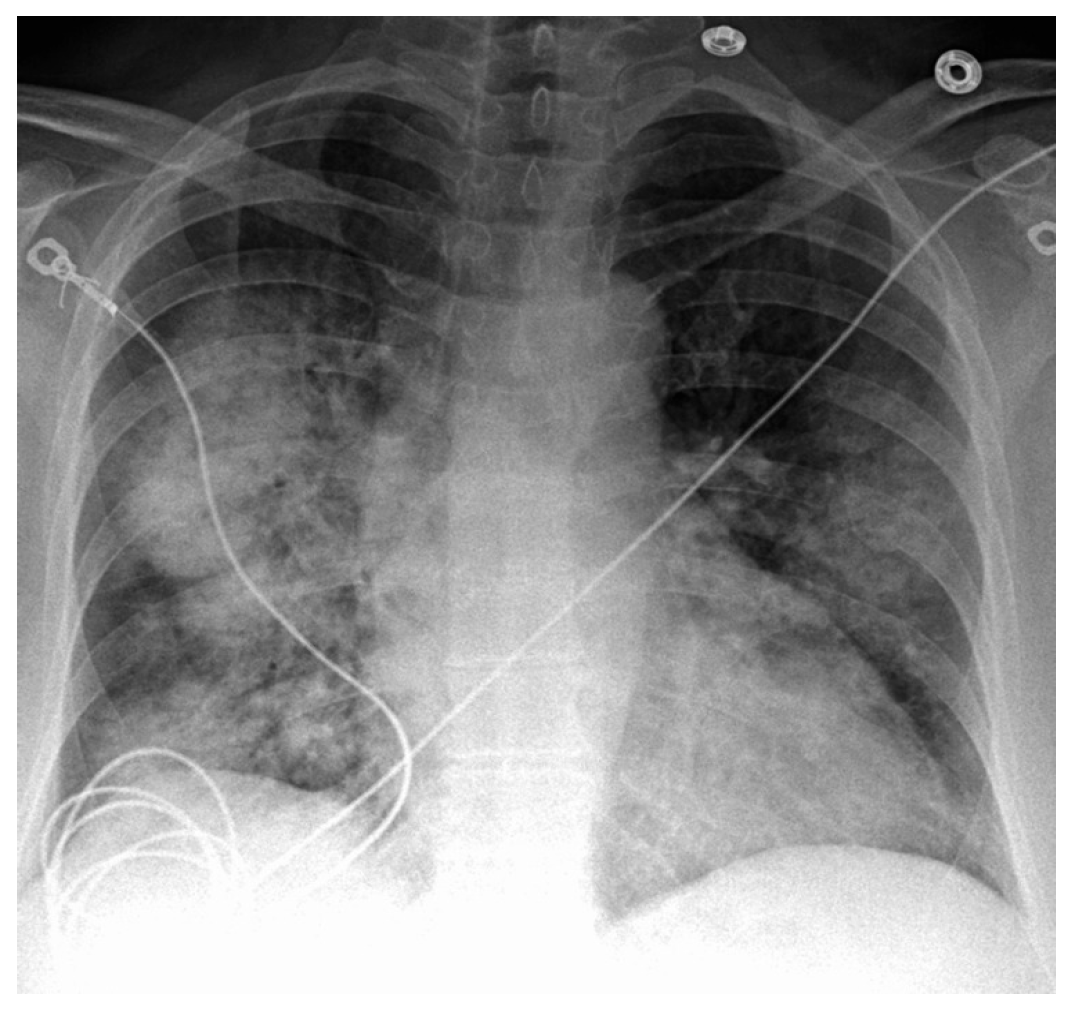

4.1. Chest X-Ray (CXR)